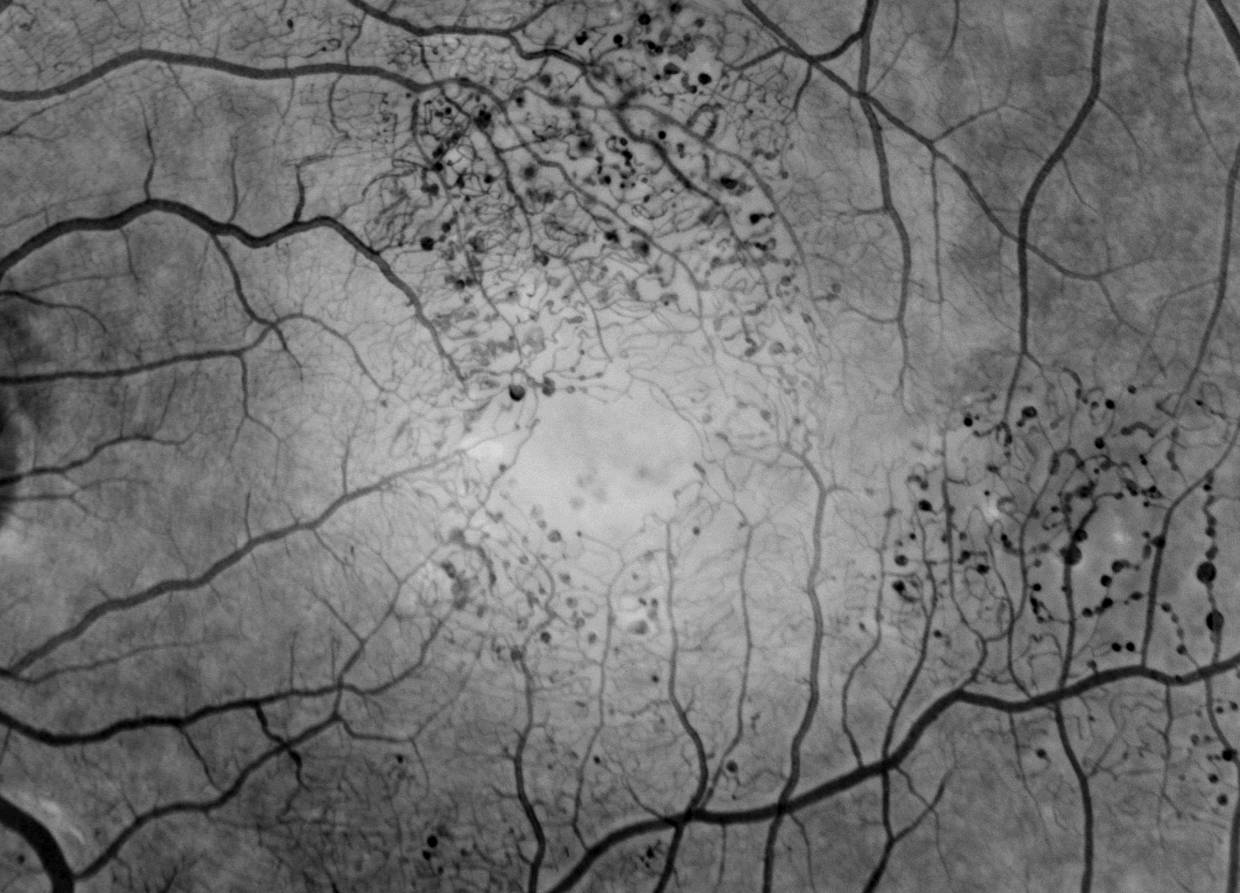

This is a fluorescein angiogram of a patient with idiopathic macular telangiectasia type 2 showing the dilated abnormal capillaries and aneurysms surrounding the center of the macula.